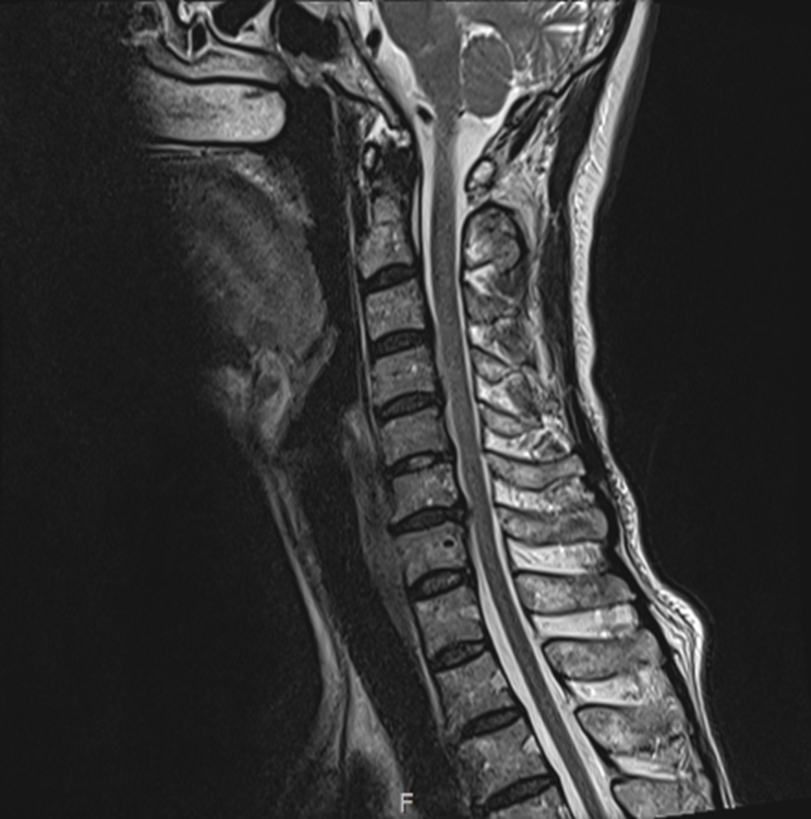

✅ 경추 4-5-6-7번에서 퇴행성 디스크 확인

✅ 다발성 협착, 특히 경추 6-7번 중심부 협착

✅ 팔신경 5, 6, 7번의 신경병증까지 동반

그림10.png 촬영 일시: 2025.06.30

<Fig 1. 경추 4-5-6-7번 협착>

환자분도, 저도 예상했던 것보다 훨씬

심각한 상태였던 거예요.

목 디스크와 협착으로 인한 신경 압박이

신경병증성 통증을 일으키고 있었던 겁니다.

머리 뒤쪽 찌릿찌릿한 통증의 진짜 범인은

뇌가 아니라 목이었던 거죠.